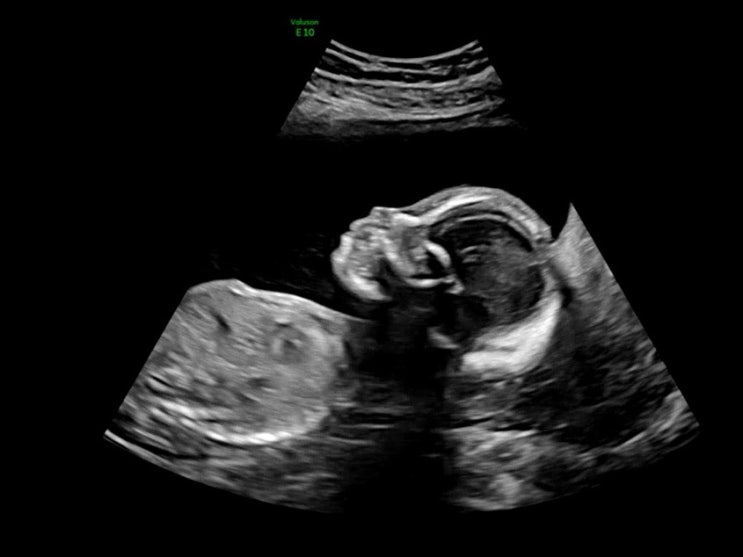

[임신 22주차] 동탄제일 정밀초음파 검사완료, 시그니엘서울 태교여행?

임신16주에 2차 기형아 검사하고 무려 6주를 기다렸다...!! 기다리는 거 너무 지루했다 ?? 드디어!! ...